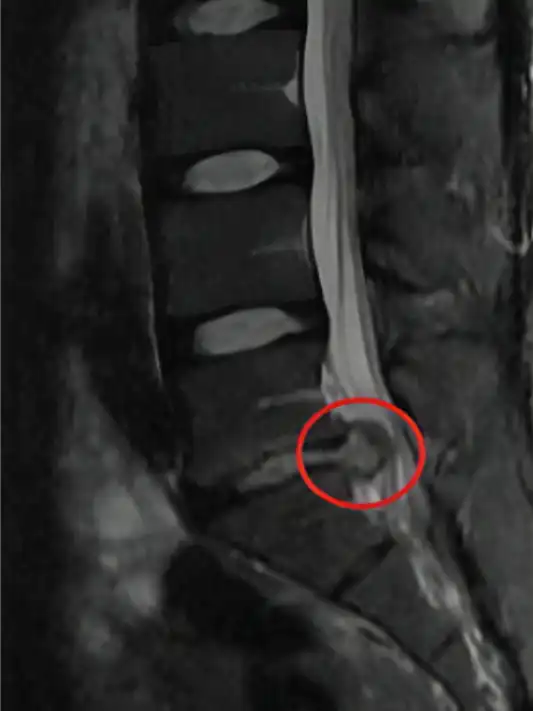

Las resonancias de un paciente antes y después de las sesiones con la bomba diamagnética. El paciente ha realizado 15 sesiones de bomba diamágnetica. Después la hernia discal ha desaparecido.

Otro ejemplo: Antes y después de 15 sesiones con la bomba diamagnética.

La hernia grande (extruida) ha desaparecido del todo (100%)